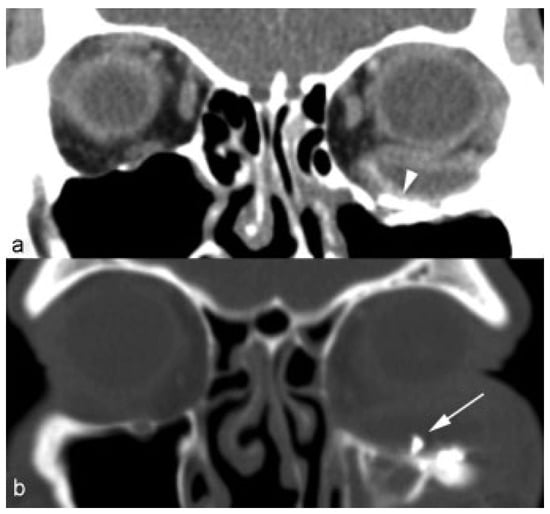

Delayed Periorbital Abscess After Silicone Implant to Orbital Floor Fracture